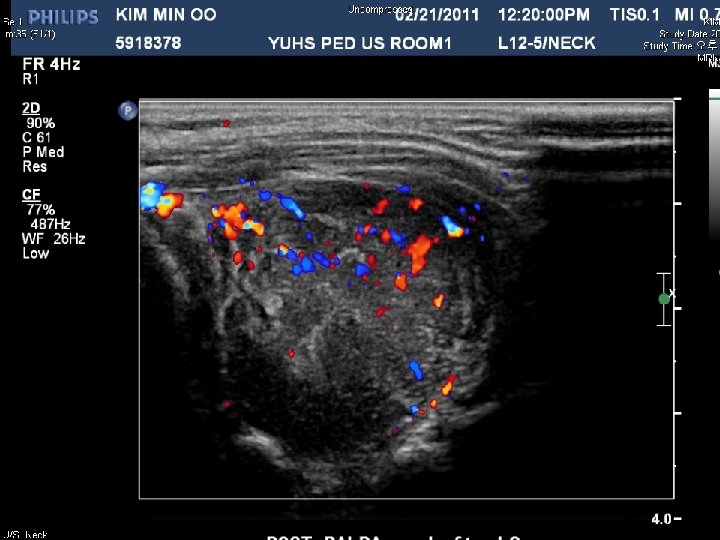

SC 11 -08587 • M/4 Soft tissue, neck, fine needle aspiration • 내원 한달 전부터 갑자기 커진 left posterior neck mass를 주소로 내원. Follow up neck sonography에서 크기가 증가되어 aspiration 시행

Final diagnosis Rhabdomyosarcoma, most likely alveolar type